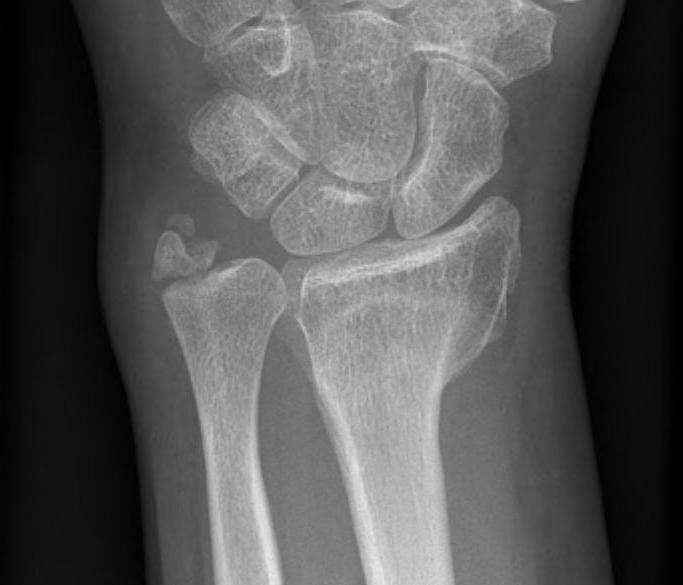

Malunion

Radial shortening Radial inclination Positive ulna variance

Xray

Bilateral xrays

PA film in neutral

- wrist neutral

- elbow & shoulder at 90°